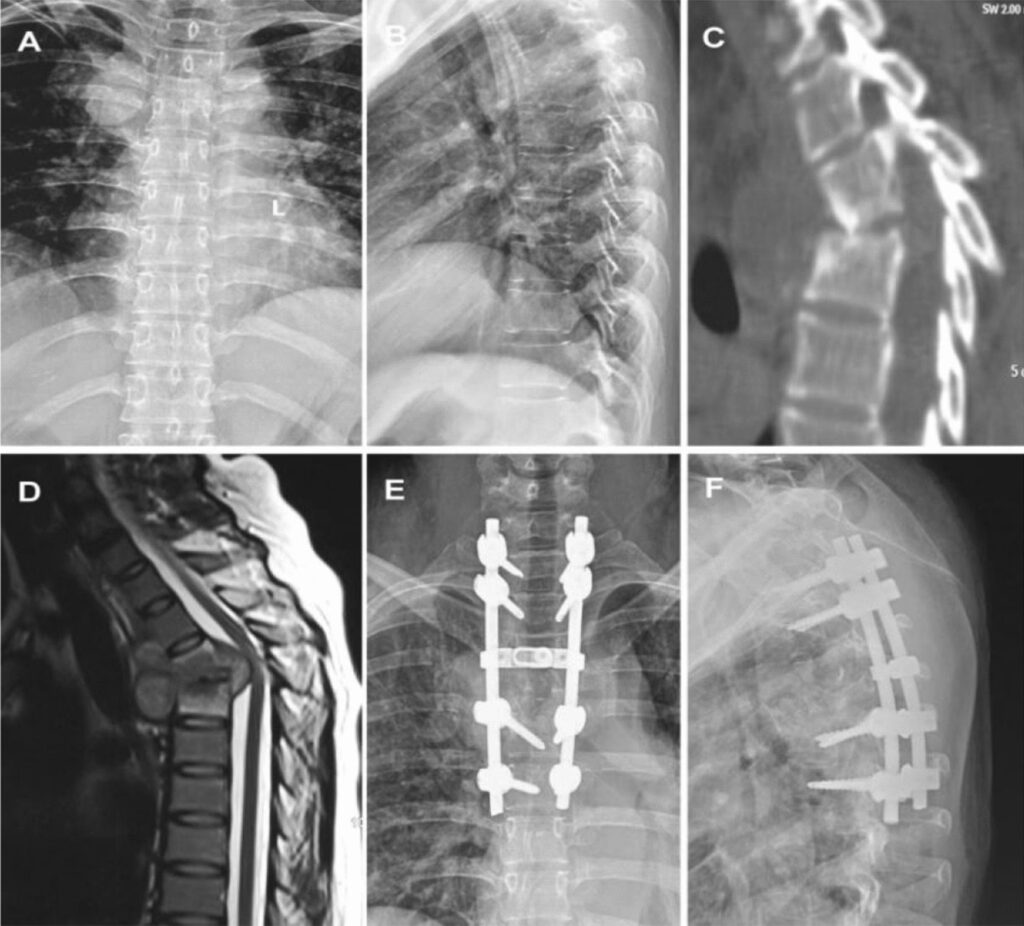

- Billeddiagnostik: En MR-scanning er den mest følsomme og specifikke metode til at diagnosticere spinal TB. Den kan vise tidlige tegn på infektion i knoglemarven, ødelæggelse af diskus, dannelse af bylder og pres på rygmarven. Røntgenbilleder kan vise knogledestruktion og deformiteter, men først når sygdommen er mere fremskreden. CT-scanninger er gode til at vurdere omfanget af knogleskaden.

Kirurgisk Indgreb

Kirurgi er ofte nødvendig i tilfælde af:

- Neurologisk påvirkning: For at fjerne trykket fra rygmarven.

- Betydelig deformitet: For at korrigere krumningen og forhindre yderligere kollaps.

- Spinal ustabilitet: For at stabilisere rygsøjlen ved hjælp af skruer, stænger og knogletransplantater.

- Store bylder: For at dræne pus og fjerne inficeret væv.